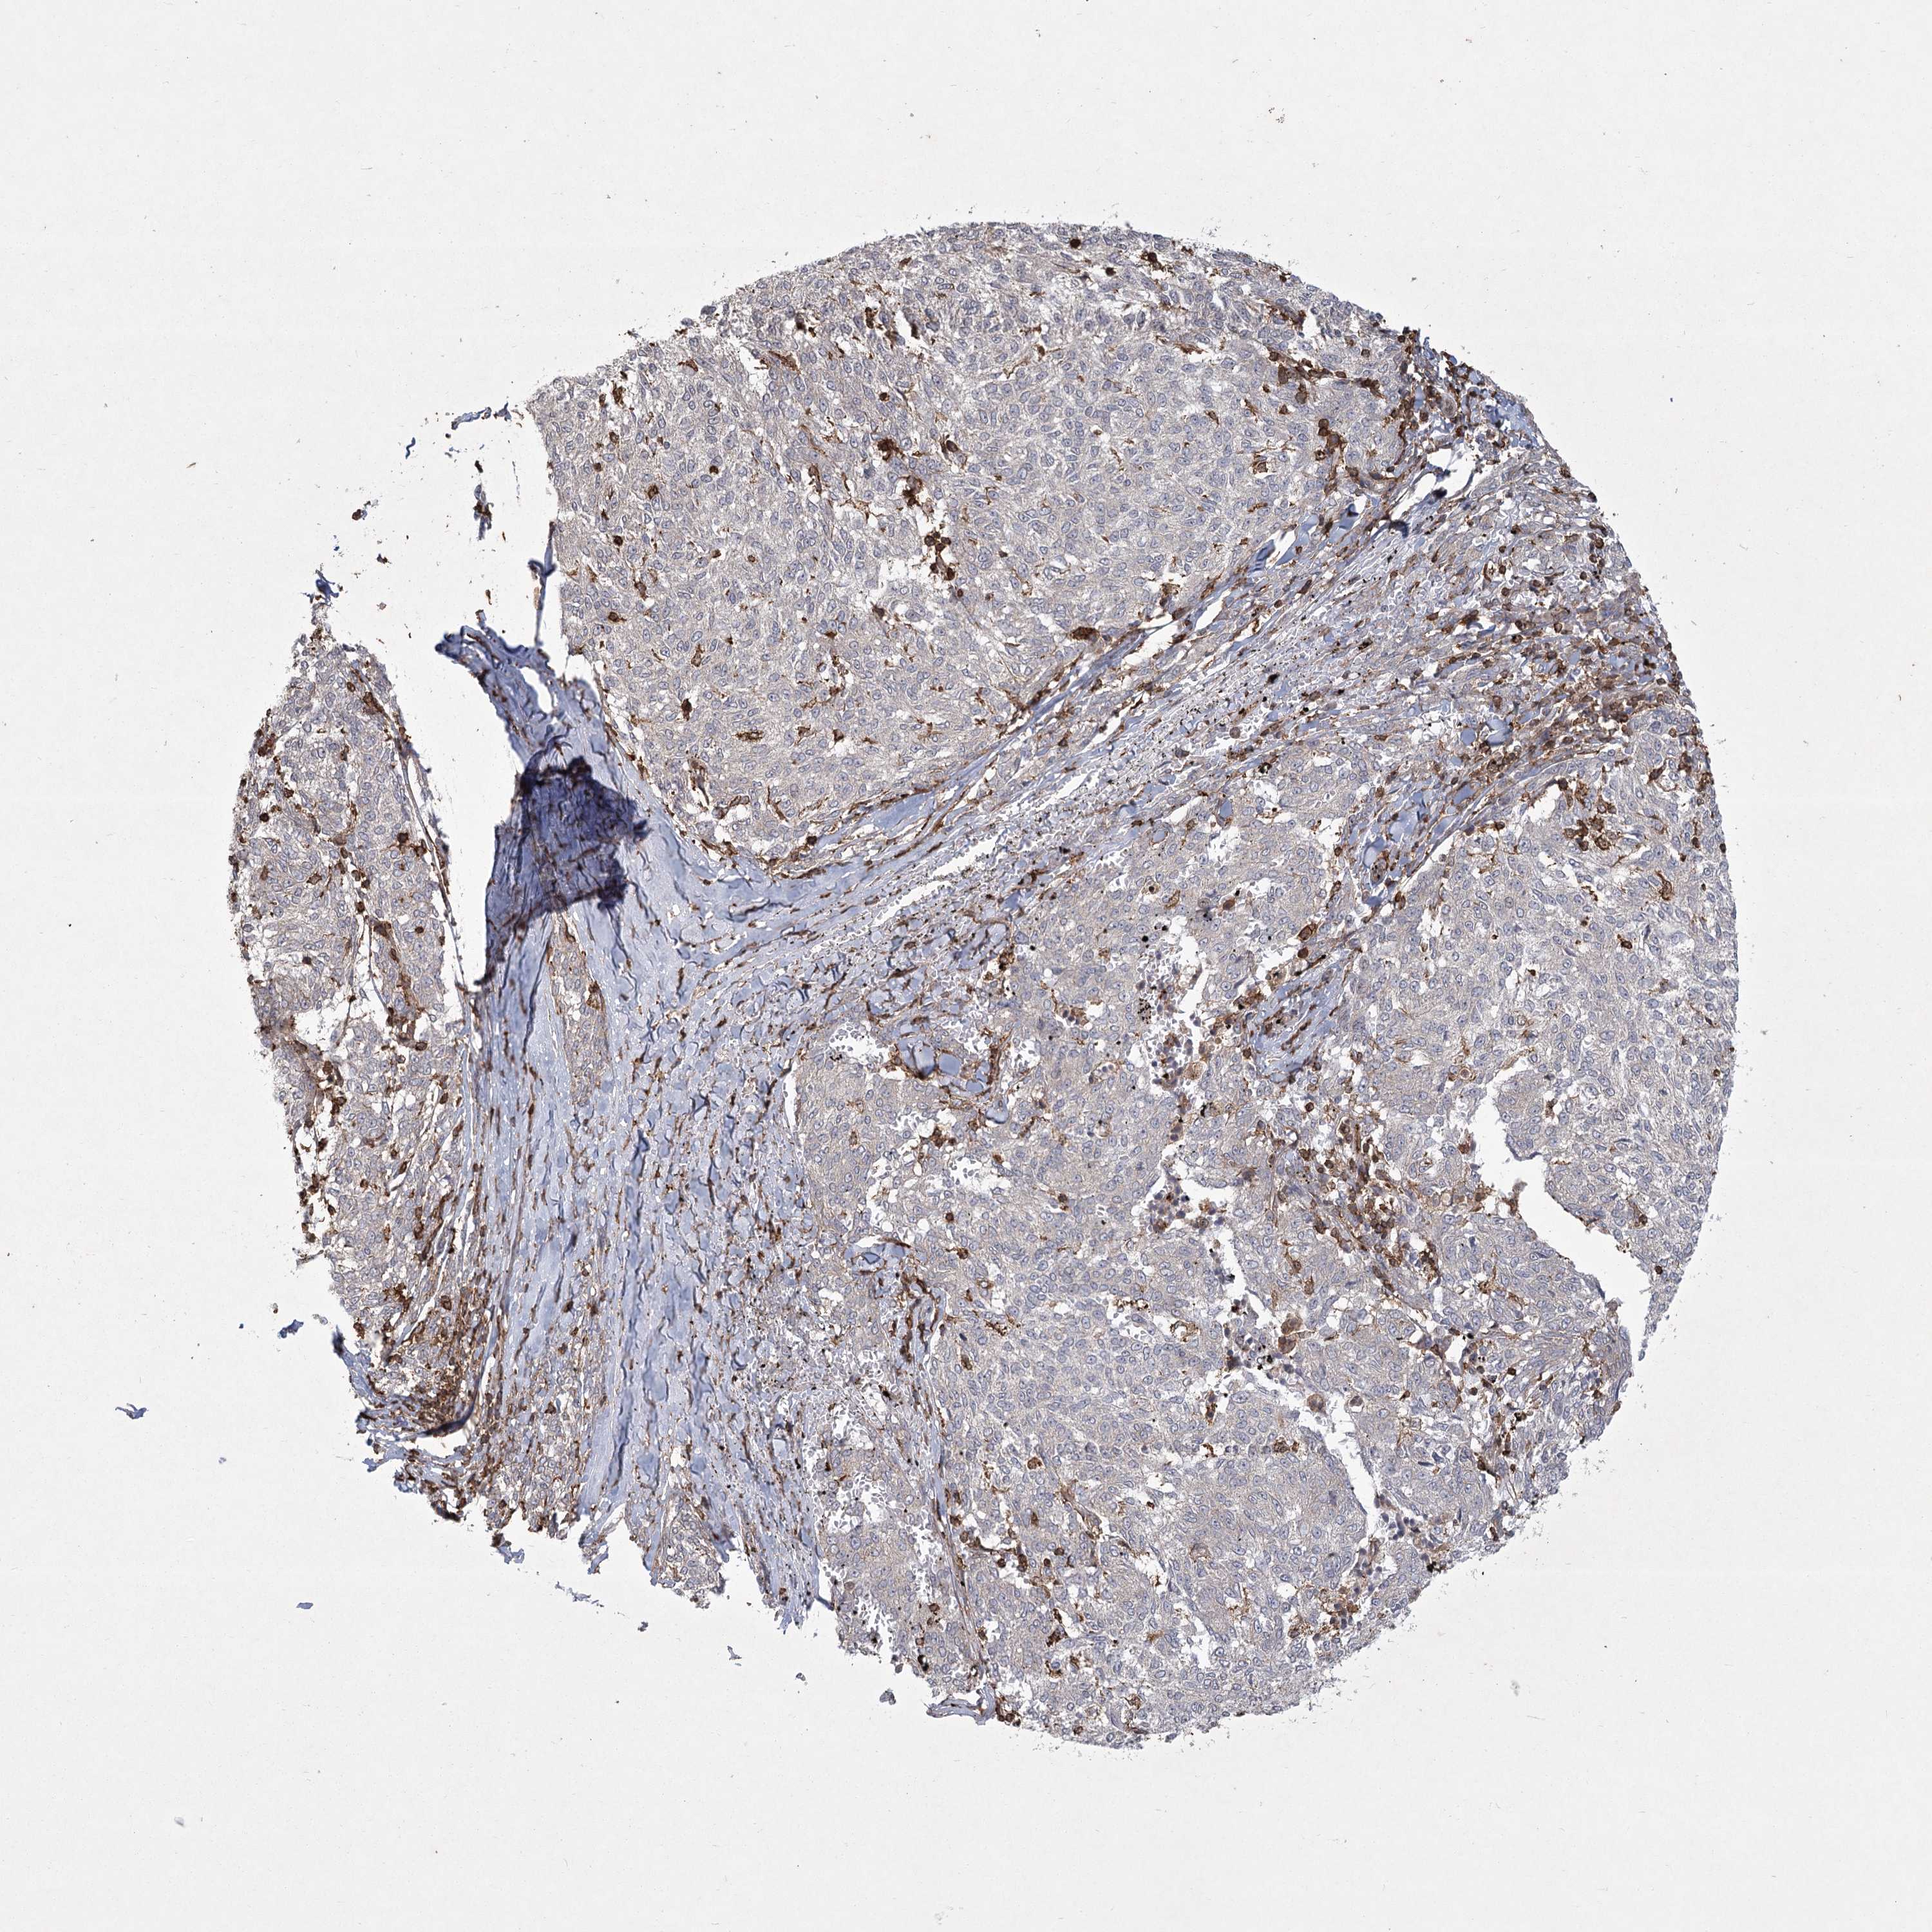

MELANOMA - Protein expressioni

A mouse-over function shows sample information and annotation data. Click on an image to view it in a full screen mode. Samples can be filtered based on level of antibody staining by selecting one or several of the following categories: high, medium, low and not detected. The assay and annotation is described here.

Note that samples used for immunohistochemistry by the Human Protein Atlas do not correspond to samples in the TCGA dataset.

Antibody stainingi

Antibody staining in the annotated cell types in the current human tissue is reported as not detected, low, medium, or high, based on conventional immunohistochemistry profiling in selected tissues. This score is based on the combination of the staining intensity and fraction of stained cells.

Each image is clickable and will lead to virtual microscopy that enables deeper exploration of all samples and also displays staining intensity scores, fraction scores and subcellular localization as well as patient and tissue information for each sample.

Antibody HPA038003

Antibody HPA038004

Staining

High

Medium

Low

Not detected

Intensity

Strong

Moderate

Weak

Negative

Quantity

>75%

75%-25%

<25%

None

Location

Nuclear

Cytoplasmic/membranous

Cytoplasmic/membranous,nuclear

Malignant melanoma, NOS

Malignant melanoma, Metastatic site